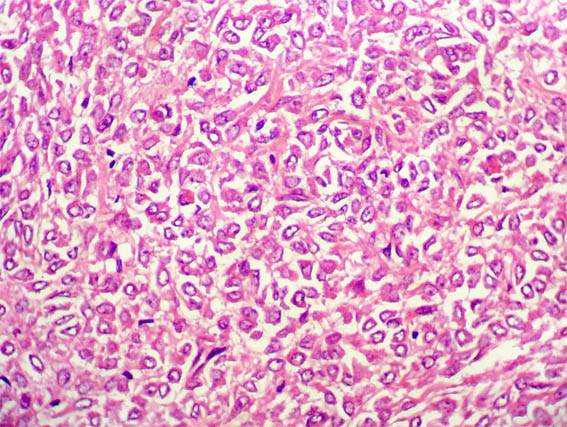

Figura 3.

H&E, X400.